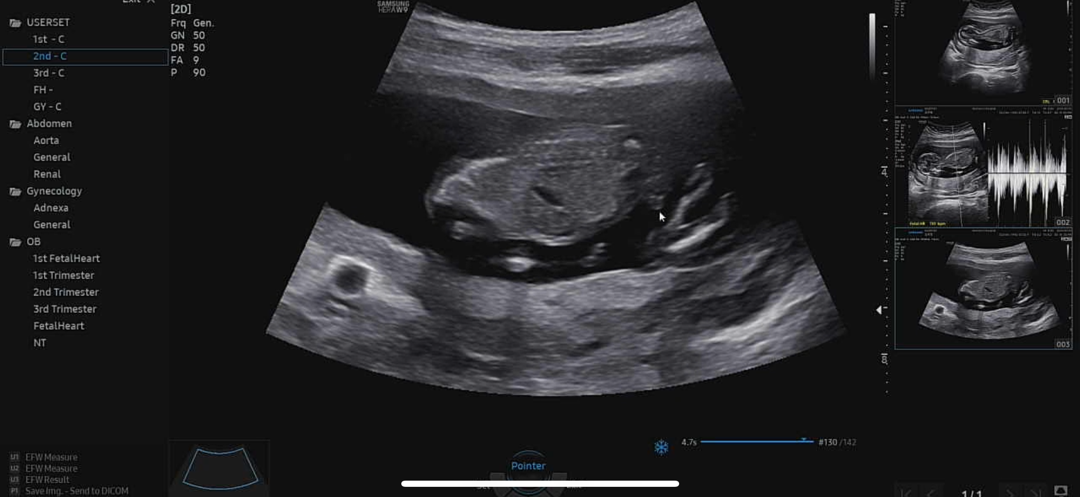

아들맞을까요?

엎드려있어서 잘안보이는데 마우스로 콕 찍어주시긴 하더라구요~ 아들 맞을까용???? 14주 촘파에요!